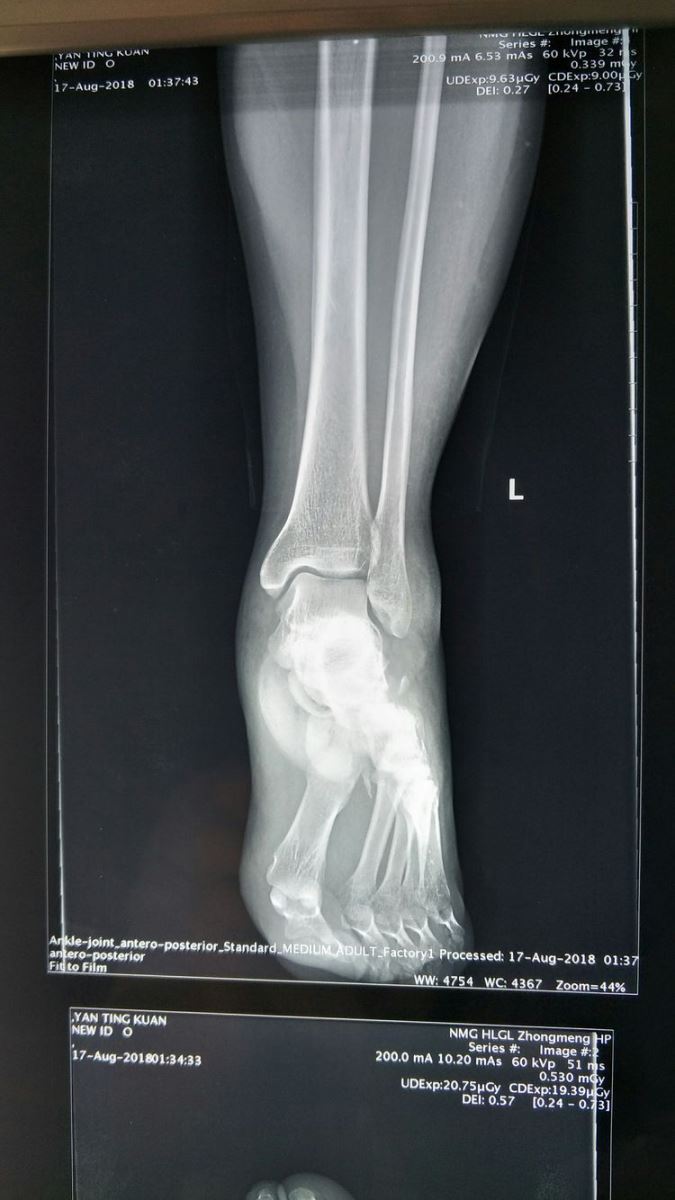

左踝关节侧位片:Chaopart关节脱位,跖跗关节脱位。

左踝关节正位片:前足向外侧移位。